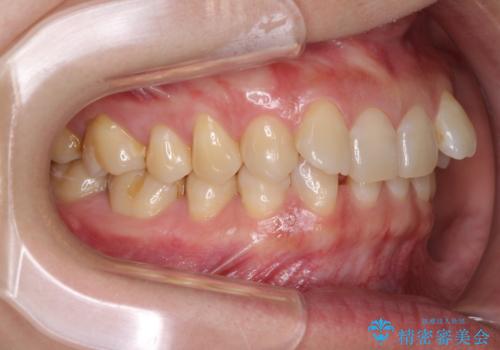

マウスピースでの抜歯矯正特有の抜歯スペースに向かって奥歯が傾斜する動きが顕著に表れ、ディープバイトは改善されませんでした。

前歯のみが強く接触し、奥歯で咬めない期間も続いたため、ワイヤー装置などを補助的に使用し、何とか終了させることができました。